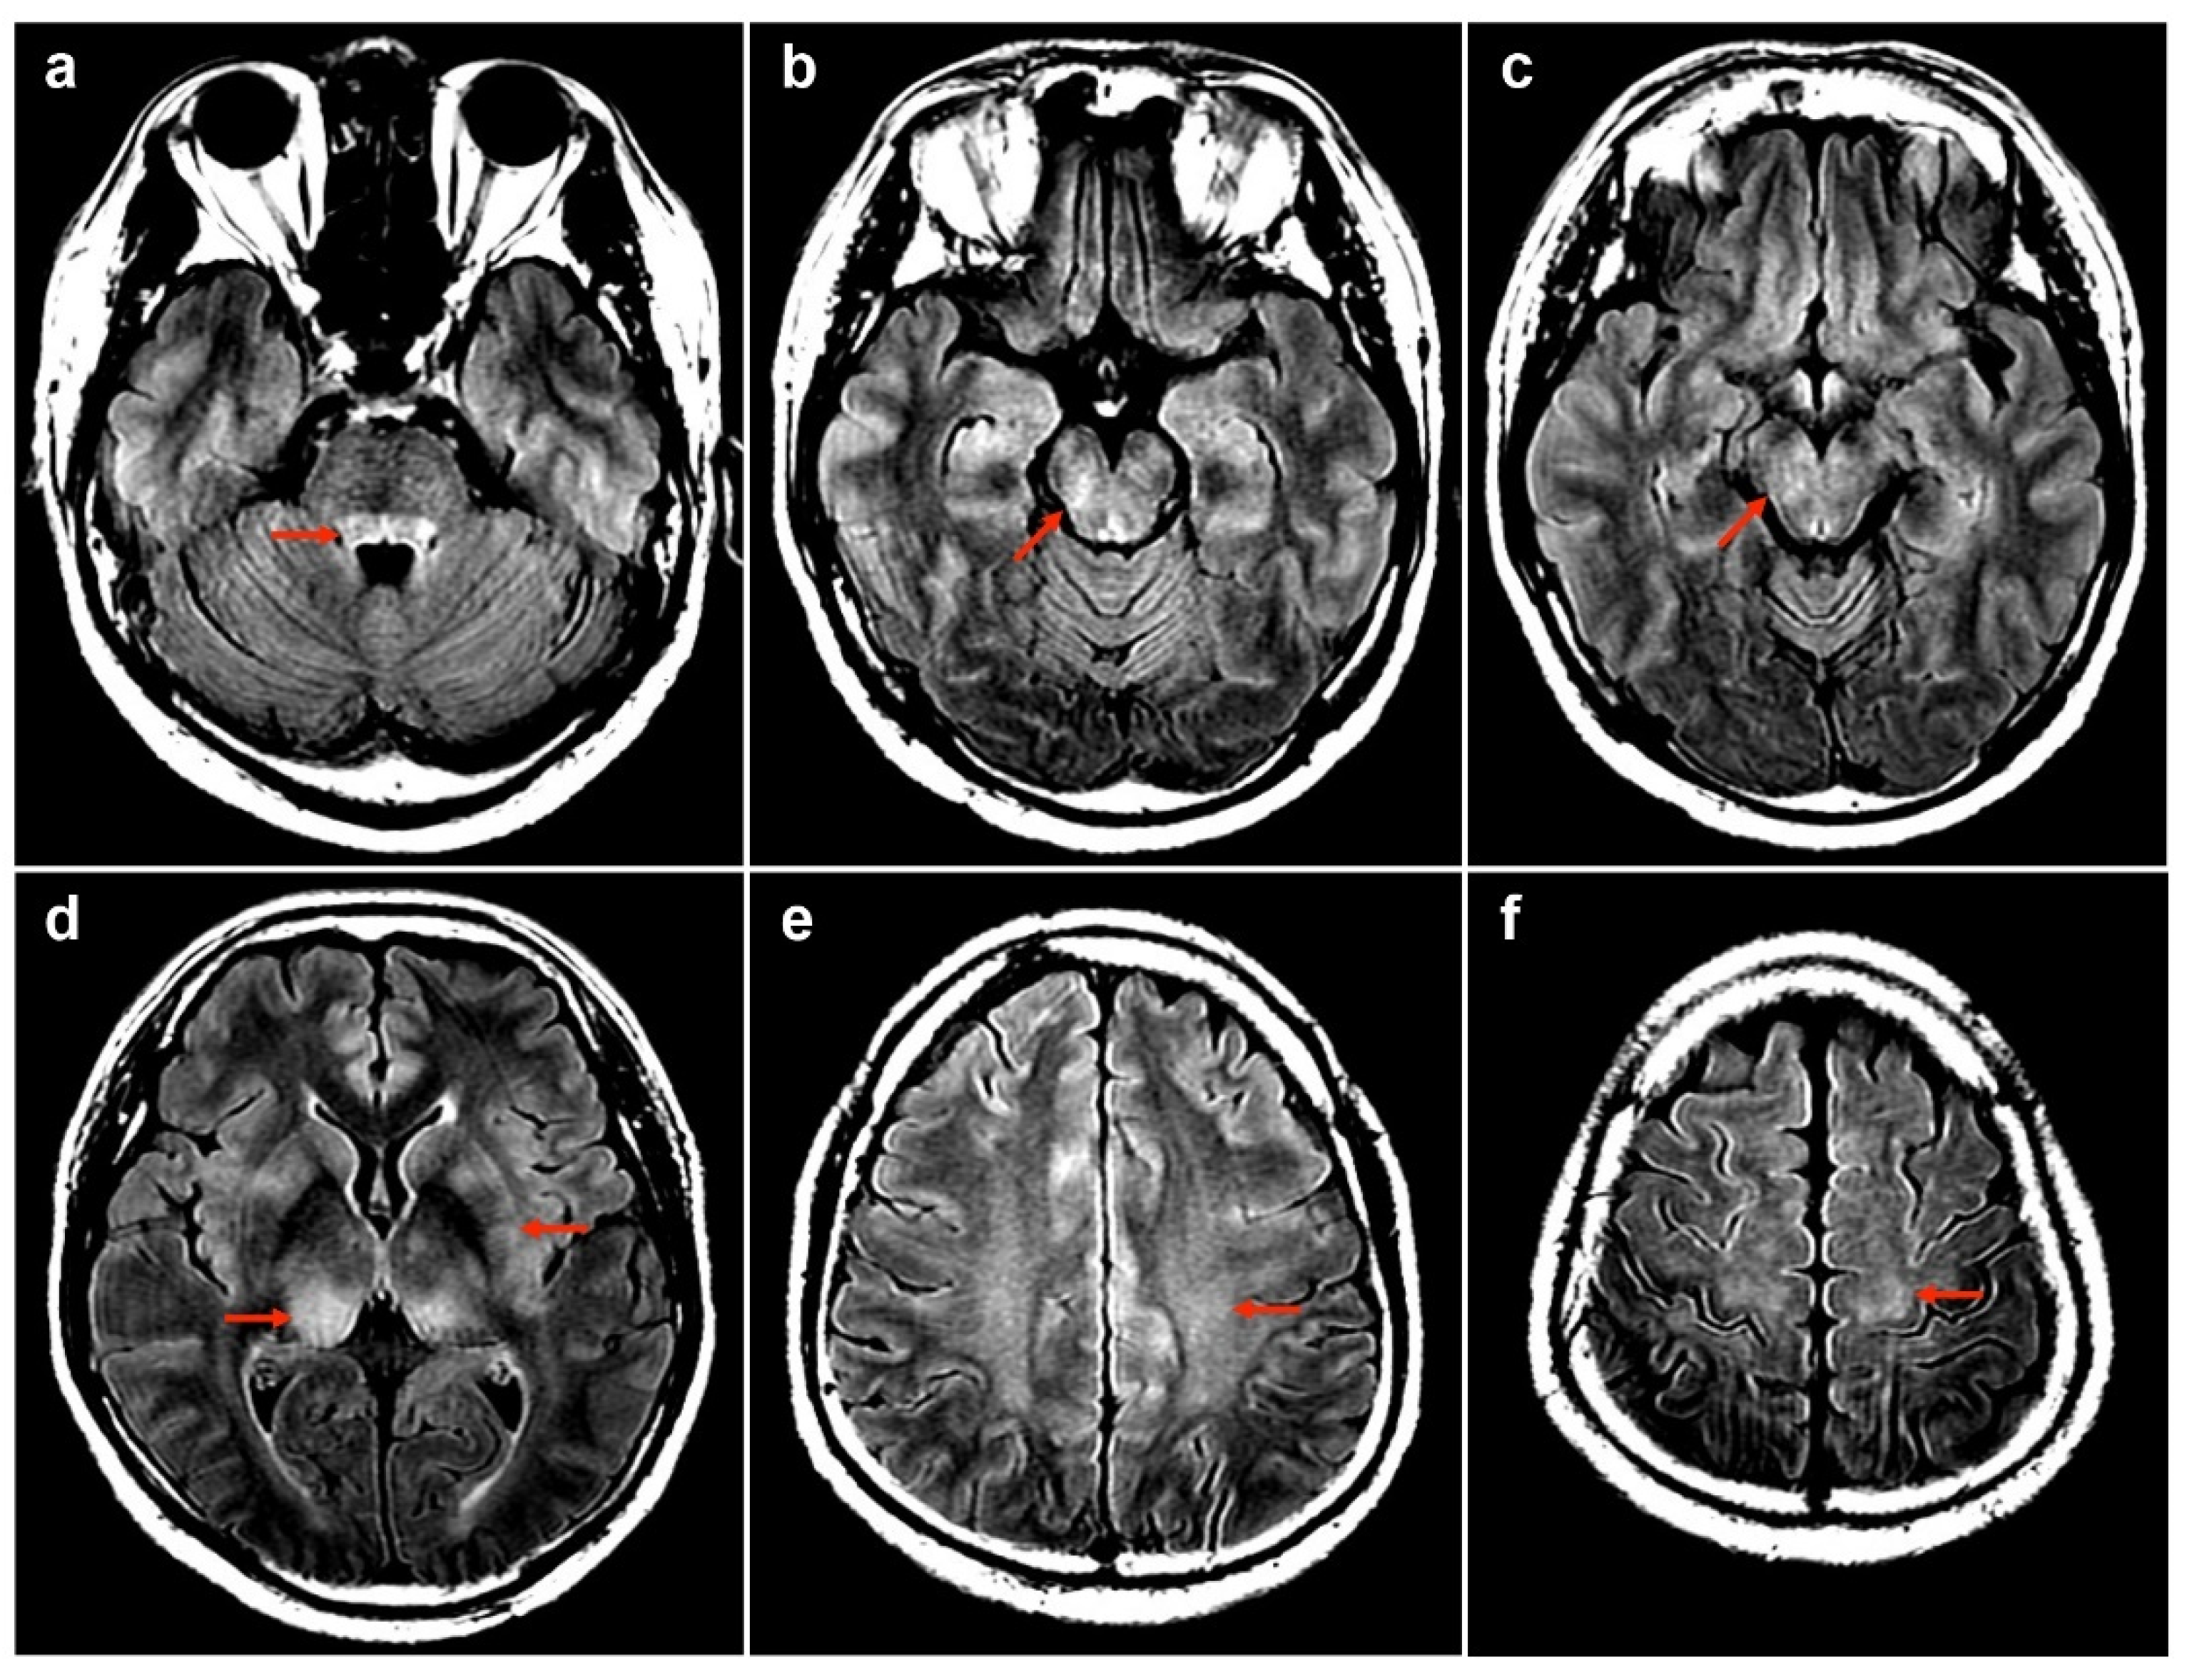

| 1 | 50M/chronic HBV | 1st AZ a/13 | MOGAD | − | + | 175 | 99 | 0 | 78.1 | 0.47 | NA | Bil thalami, pu, subcortical WM, brainstem | T3–T4 | PT | R | Index case |